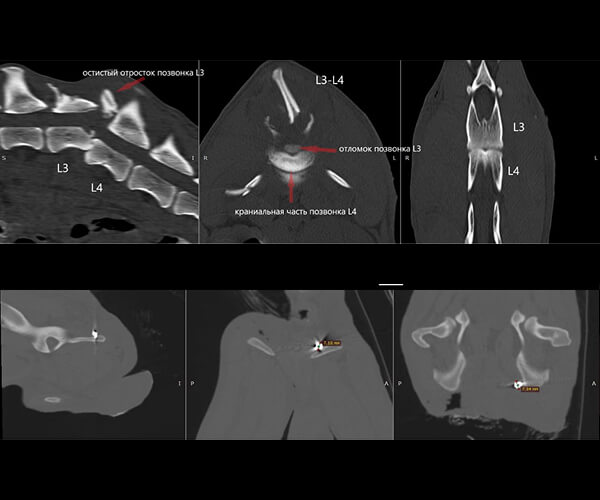

Именно в этот момент над Зухраем надругались люди. Сначала с него сдирали кожу по бокам. Потом били по спине. А позже — выстрелили. На КТ видно: в теле Зухрая застряли пули, позвоночник повреждён, задние лапы отказали. Судя по снимкам, спинной мозг разорван. Сегодня он не может лечь. Он спит и ест только сидя, каждую минуту испытывая боль.